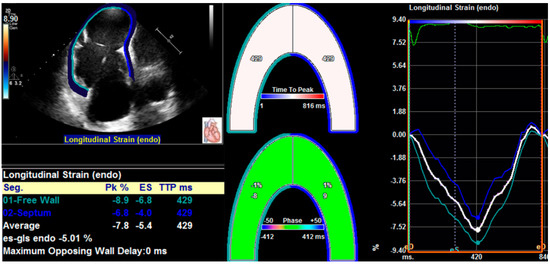

3.3. Three-Dimensional Speckle Tracking Echocardiography

More recently, three-dimensional speckle tracking echocardiography (3D-STE) has been introduced as a novel technique than can track the myocardial motion within the 3D volume. Thus, 3D-STE is free of geometric assumptions and out-of-plane motion of the speckles, allowing a more accurate and comprehensive evaluation of myocardial function owing to overcoming the limitations of 2D-STE [35,38,65,66]. Three-dimensional STE analysis for the right ventricle is shown in Figure 2. Its accuracy and reproducibility in assessing RV function have been confirmed in patients with transplanted hearts, pulmonary hypertension, and hypoplastic left heart syndrome after Fontan palliation [63,67,68,69]. Moreover, we previously investigated the feasibility and accuracy of 3D-STE for the quantification of RVLS in comparison with CMR imaging in a large number of study populations with a wide variety of RVEF and cardiovascular pathologies, and found that the 3D-RVFWLS values correlated better than 2D-RVFWLS values with CMR values (0.85 vs. 0.64) with smaller bias and narrower limits of agreement. Our findings demonstrated the superiority of 3D-RVFWLS over 2D-RVFWLS in evaluating RV function against CMR imaging [70,71]. However, 3D-STE also has several limitations, such as low temporal resolution and dependence on image quality [35,64].

Figure 2. Longitudinal strain of the RV free wall and septum using three-dimensional speckle tracking echocardiography. (A) Setting reference points; (B,C) RV endocardial border tracking; (D) Longitudinal strain of RV free wall and septum were automatically generated.